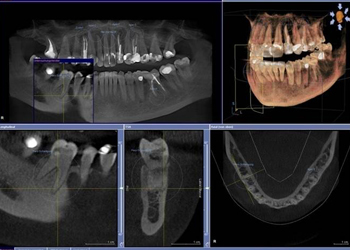

治療前治療後

| 治療内容 | インプラント奥歯1本・根管治療・矯正治療(圧下) |

|---|---|

| 患者様の年齢 | 40歳 |

| 患者様の性別 | 男性 |

| 治療期間 | 1年 |

| 治療回数 | 矯正治療合わせて50回程度 |

| 治療費用 | 根管治療1歯6万円/インプラント治療1歯50万円 矯正治療:1歯 10万円 |

| 治療で得られるメリット |

|

| 治療する際に起こる リスク・副作用 |